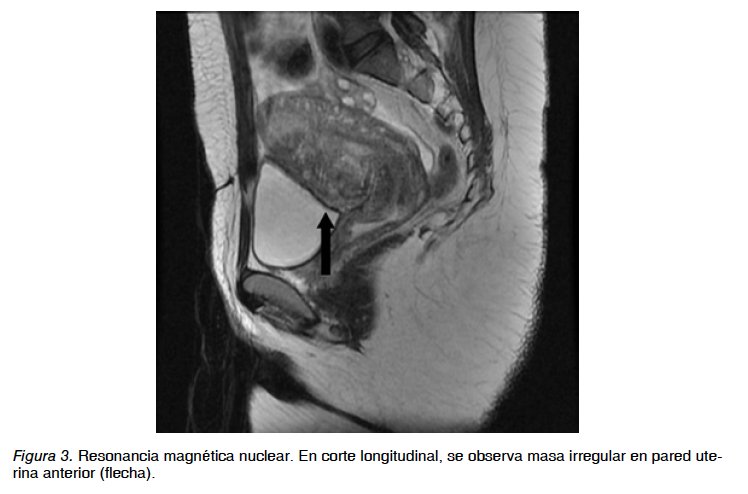

Paciente de 30 años con antecedente de embazo previo llevado a cesárea por desproporción céfalo pélvica 5 años antes. Consulta por malestar general y signos de respuesta inflamatoria sistémica, al examen físico tacto vaginal normal, histerosonografía y resonancia magnética que reportan masa sólida dependiente de pared uterina anterior, ubicada a nivel ístmico hacia la izquierda, con límites mal diferenciados, de bordes irregulares, diámetro mayor de 3,5 cm (Figuras 1 a 4). Se realiza diagnóstico de embarazo ectópico sobreinfectado para el cual recibe tratamiento antibiótico de amplio espectro más legrado obstétrico. Cuatro semanas después la paciente continua con reactantes de fase aguda elevados, dolor pélvico y malestar general por lo que es llevada a histeroscopia diagnóstica donde se encuentra istmocele con diámetro mayor de 3 cm conteniendo masa mal definida, irregular, de aspecto necrótico e inflamatorio que invade miometrio en cara anterior. Se realiza resección de un segmento de la lesión, toma de biopsia y corrección de márgenes del defecto de cicatriz previa (Figura 5). Por la amplitud, la profundidad del defecto y la invasión trofoblástica al miometrio, se continua la resección de la masa por vía laparoscópica, logrando retirar todo el tejido comprometido (Figura 6). Se realiza histerorrafia con endosutura barbada en 2 planos (Figura 7). La paciente es dada de alta al día siguiente sin complicaciones. El reporte final de patología reporta escasas vellosidades coriales y células trofoblásticas con severos cambios degenerativos, abundante material fibrinohemorrágico y necrótico e infiltrado inflamatorio de neutrófilos.

La ecografía transvaginal es la herramienta de primera línea con una sensibilidad del 86,4%, reporta cavidad uterina y canal cervical vacíos sin contacto con saco gestacional y detección en la pared anterior del istmo uterino del saco gestacional con presencia o no de embrión (6). Otros métodos de imagen o quirúrgicos como la resonancia magnética, ecografía tridimensional, histeroscopia o laparoscopia también son útiles en el diagnóstico (7).